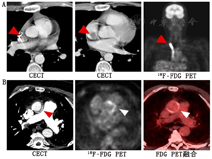

2.心血管系统感染。近年研究显示,核医学影像,特别是与结构影像结合的技术在心血管系统感染诊断中起着重要作用。虽然核医学影像一般仅用于其他影像方法无法诊断的情况或评估并发症和治疗反应,但其在心血管疾病中的应用正在不断拓展[39]。2015年,根据人工瓣膜心内膜炎Duke标准,核素标记的WBC SPECT/CT和18F-FDG PET/CT作为辅助方法被纳入欧洲心脏病学会感染性心内膜炎指南,用于协助诊断可能的感染性心内膜炎,同时检测心外感染灶和监测治疗反应[40]。无论有无症状,18F-FDG PET/CT可在约40%的感染性心内膜炎患者中检出阳性栓子[39],但栓子小于5 mm时易出现假阴性,术后非特异性显像剂摄取可能会使其应用受限[40]。相比之下,核素标记WBC SPECT/CT灵敏度较低,但更具特异性,即便在术后也不受影响[41]。上述2种显像方法联合应用时,特异性近100%,充分展示了多种显像协同作用的优势[40,42]。图3为1例59岁感染性心内膜炎患者的18F-FDG PET/CT图像示例。